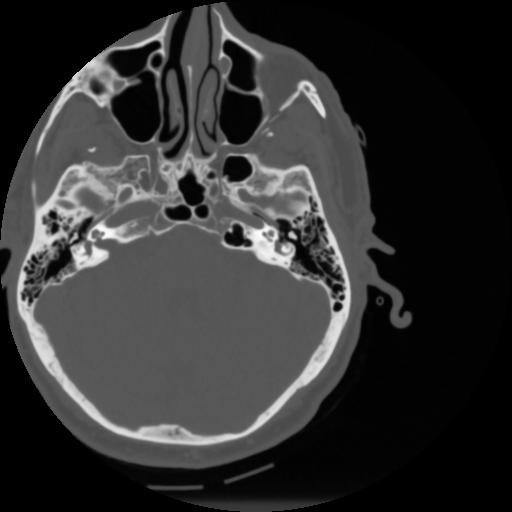

4 CEREBRO,,Vol,0.5,CEREBRO,,